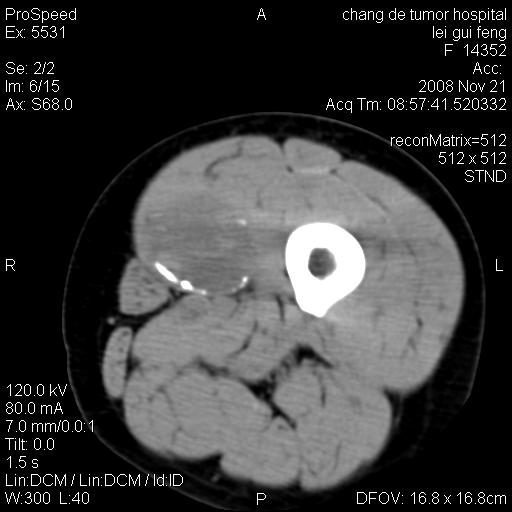

标题: CT16807:女 41 无不适 [打印本页]

标题: CT16807:女 41 无不适

考虑皮样囊肿可能性大

血管瘤可能

血管瘤

血管瘤可能性大!

黏液瘤或表皮杨囊肿

不排除横纹肌肉瘤可能。

血管瘤可能性大或畸胎瘤

考虑脂肪肉瘤

考虑血管瘤可能性大;不排除肉瘤可能。建议行活检。

脂肪肉瘤?

双是软组织肿瘤,病灶内多发钙化,另可见多量脂肪密度影,考虑畸胎瘤,血管瘤,不除外其他